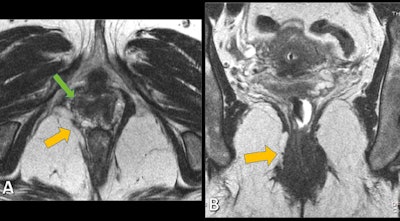

Static axial (A) and coronal (B) T2-weighted MR images allow the identification of structural defects, as disruption of right puborectalis muscle (yellow arrows) and loss of H-shaped vagina on the right side (green arrow). Images courtesy of Dr. Patrícia Costa. © Hospital Pedro Hispano, Hospital Pedro Hispano - Matosinhos/PT.Quality-of-life impairment